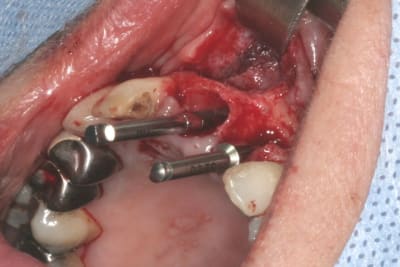

tien, ce matin, extraction de 24/25, curetage méticuleux, forage, comblement du gap, pose des 2 implants qui se sont bloqués à 50Ncm au CA sur les 3 ou 4 mm apicaux, pose des vis de cicat, sutures...35min....tranquille...

Si conique à 12° comme le Nobel Active...

oui, ils peuvent te reprendre ton stock de legacy3, tout comme les pièces prothétiques non utilisées (blister intact) bien sûr...

tu gardes ta trousse par contre, tu n'auras qu'a acheter les instruments d'insertion pour CA et pour la clef à cliquet (les longs)

donc: hex tool pour CA en 2.3mm et 2.7mm (2 plateformes prothétiques 2.3 rouge/violet et 2.7 jaune) et hex tool long en 2.3 et 2.7mm pour la clef

perso, j'ai totalement switché sur l'interactive

tu auras en plus 2 bonus:

la partie colorée du pilier est clipsée...plus besoin de disque carbo...en plus pour l'empreinte çà permet une empreinte fermée clipée quasi aussi précise qu'une à ciel ouvert...

autre bonus: tes vis ne tomberont plus...il y a de nouveau le filetage dans le moignon (bein oui qui dit conique dit plus de friction...et donc filetage dans la pièce prothétique au cas où...pour les instruments de désinsertions à visser, comme feu le TRLT2 zimmer)

par contre chaque plateforme prothétique à son propre diamètre de vis...donc 2 différentes...